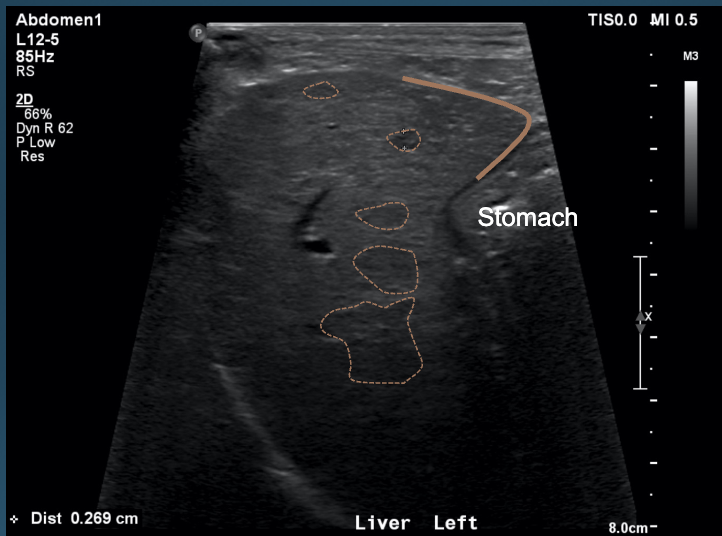

What is shown in these images?

A

normal liver; normal gastric axis